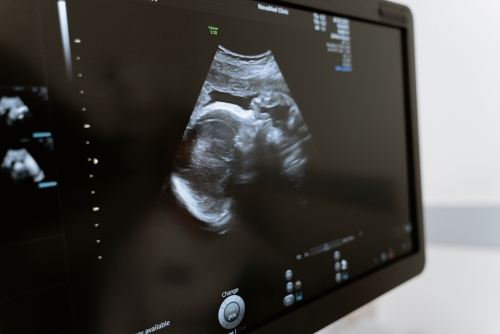

超聲檢查室并不是只有一個,而是一個具有多個功能的輔助檢查室,包括超聲科、影像科、醫學科等。超聲檢查室主要可以用來檢查心臟、甲狀腺、淋巴結、乳腺、血管等器官,明確是否存在病變。

1、心臟:通過超聲檢查可以對心臟的結構、大小、形態、位置,以及收縮和舒張功能進行測量,還可以測量心臟血流。通過超聲心動圖可以測量出心臟瓣膜的反流,以及心臟血流增加的程度;

2、甲狀腺:通過超聲檢查可以對甲狀腺的大小、形態、位置,以及血流情況進行測量,還可以明確甲狀腺結節的大小,對于判斷甲狀腺功能亢進癥具有較大的輔助作用;

超聲檢測2

3、淋巴結:可以對淋巴結的大小、形態、位置,以及血流進行測量,淋巴結增大時可見于急性感染,如急性咽喉炎、急性扁桃體炎。如果淋巴結呈現淋巴結腫大的情況,可能為惡性腫瘤轉移所致;

4、乳腺:可以對乳腺的大小、形態、位置,以及血流進行測量,還可以明確乳腺結節的性質;

5、血管:超聲檢查可以對血管的管徑進行測量,還可以觀察血管內的流速,對于診斷血管瘤具有較大的幫助。

除上述超聲檢查室外,其他臟器組織超聲檢查室也可以用于對部分腫瘤、占位性病變以及其他疾病的輔助診斷。例如肝臟超聲檢查室可以用于檢查肝臟血管瘤,膽囊超聲檢查室可以用于檢查膽囊結石、膽囊息肉等。